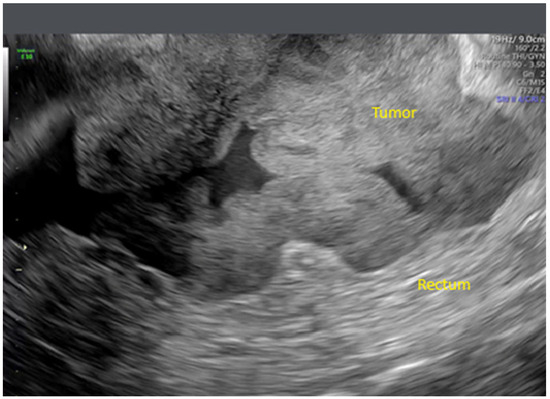

- Zikan, M.; Fischerova, D.; Semeradova, I.; Slama, J.; Dundr, P.; Weinberger, V.; Dusek, L.; Cibula, D. Accuracy of ultrasound in prediction of rectosigmoid infiltration in epithelial ovarian cancer. Ultrasound Obstet. Gynecol. 2017, 50, 533–538. [Google Scholar] [CrossRef]

- Fischerova, D.; Zikan, M.; Semeradova, I.; Slama, J.; Kocian, R.; Dundr, P.; Nemejcova, K.; Burgetova, A.; Dusek, L.; Cibula, D. Ultrasound in preoperative assessment of pelvic and abdominal spread in patients with ovarian cancer: A prospective study. Ultrasound Obstet. Gynecol. 2017, 49, 263–274. [Google Scholar] [CrossRef]

- Fischerová, D.; Pinto, P.; Burgetová, A.; Masek, M.; Sláma, J.; Kocián, R.; Frühauf, F.; Zikán, M.; Dušek, L.; Dundr, P.; et al. Preoperative staging of ovarian cancer: Comparison between ultrasound, CT and whole-body diffusion-weighted MRI (ISAAC study). Ultrasound Obstet. Gynecol. 2022, 59, 248–262. [Google Scholar] [CrossRef]